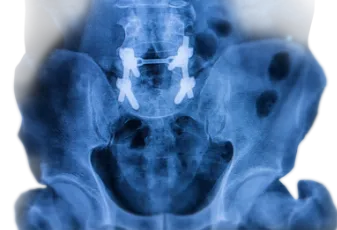

החלפת מפרק ירך

ניתוח החלפת מפרק הירך – המדריך עם כל המידע הרפואי והמעודכן מפרק הירך, הוא המפרק המחבר בין עצם הירך שבמעלה הרגל לעצמות האגן, הוא מפרק כדורי עדין יחסית, הנושא בחלק ניכר מעומסי המשקל והתנועה של הגוף. כמו במפרקים אחרים בגוף, גם כאן מוכ